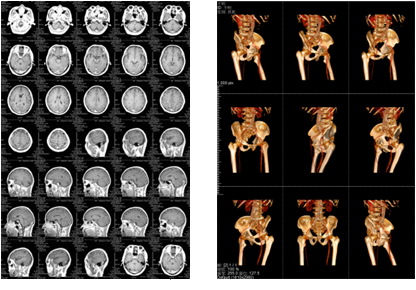

該三甲醫(yī)院放射科負責日常CT、核磁共振影像的輸出,平均的日打印量在1000張左右。在導入解決方案前,該放射科的影像輸出使用干式膠片打印傳統(tǒng)膠片,輸出設備價格不菲,而且傳統(tǒng)膠片價格更是高昂。另外,傳統(tǒng)膠片不能實現彩色輸出,醫(yī)生必須在背光板上進行診斷,膠片本身還含有重金屬等有毒物質,污染環(huán)境。為此,柯尼卡美能達向專業(yè)供應商采購了DICOM轉換服務器和符合醫(yī)院要求的打印膠片紙,可實現三維打印,打印的影像可直接在自然光下觀看,便于醫(yī)生診斷;膠片紙的成本是傳統(tǒng)膠片的三分之一而且不含毒物質,既節(jié)省成本又綠色環(huán)保。

膠片紙輸出樣張示意